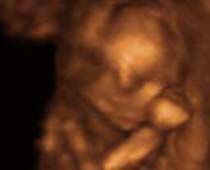

- 3D Photos échographie du comportement du fœtus

- Le comportement du fœtus pendant la grossesse

- Commencer l'album photo de votre bébé